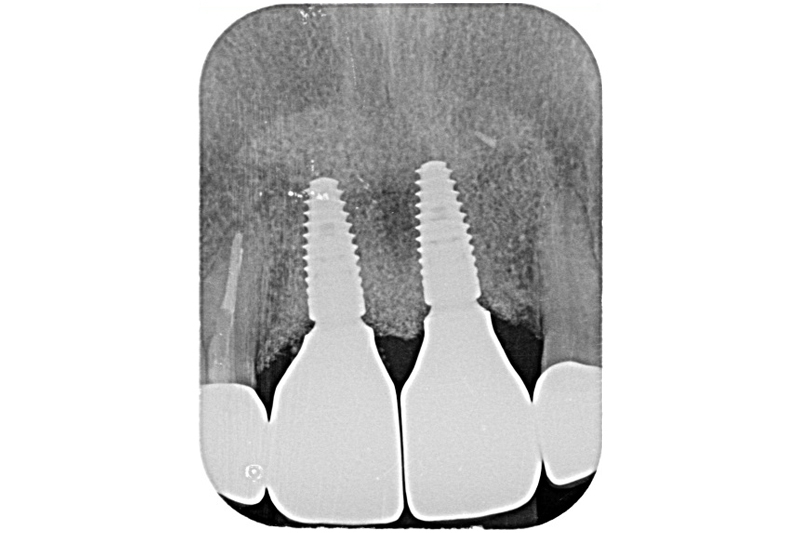

初診環口X光片檢測可見植體的角度位置都不理想,齒槽骨有吸收的現象。建議患者先接受牙周病的第一階段治療,進行感染控制

根尖X光片術前

根尖x光片術後